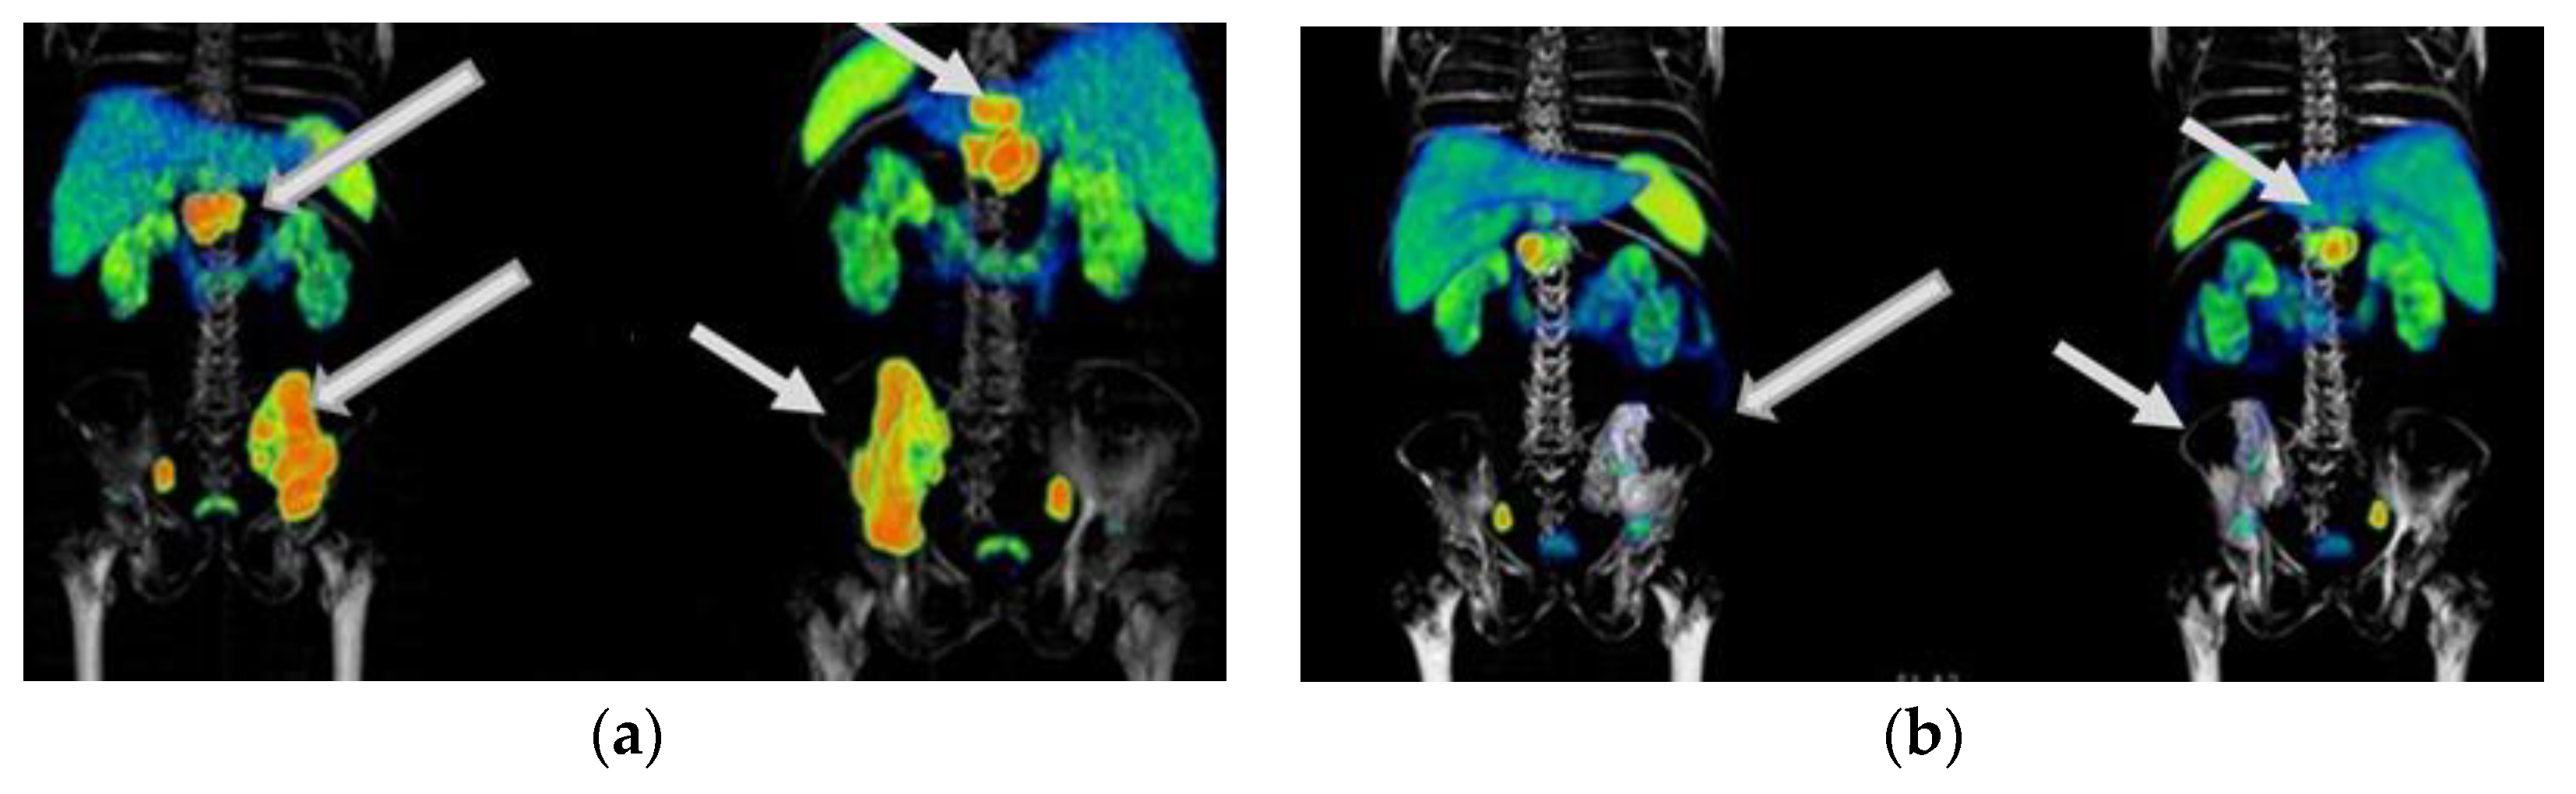

Figure 7. A 48-year-old woman was diagnosed with a metastatic neuroendocrine tumor of the ileum. She received 177Lu-DOTATOC (four doses of 7.4 GBq) in combination with octreotide. Response: stable disease. No hematologic or renal toxicity. (a) 68Ga-DOTATOC PET/CT imaging before 177Lu-DOTATOC therapy, (b) 177Lu-DOTATOC SPECT imaging (first dose), (c) 68Ga-DOTATOC PET/CT imaging one year after the first dose of 177Lu-DOTATOC.

Figure 6, Figure 7 and Figure 8 show typical clinical cases of partial response and stable disease after 177Lu-DOTATOC therapy (the stable disease does not meet the criteria for partial response or progressive disease).